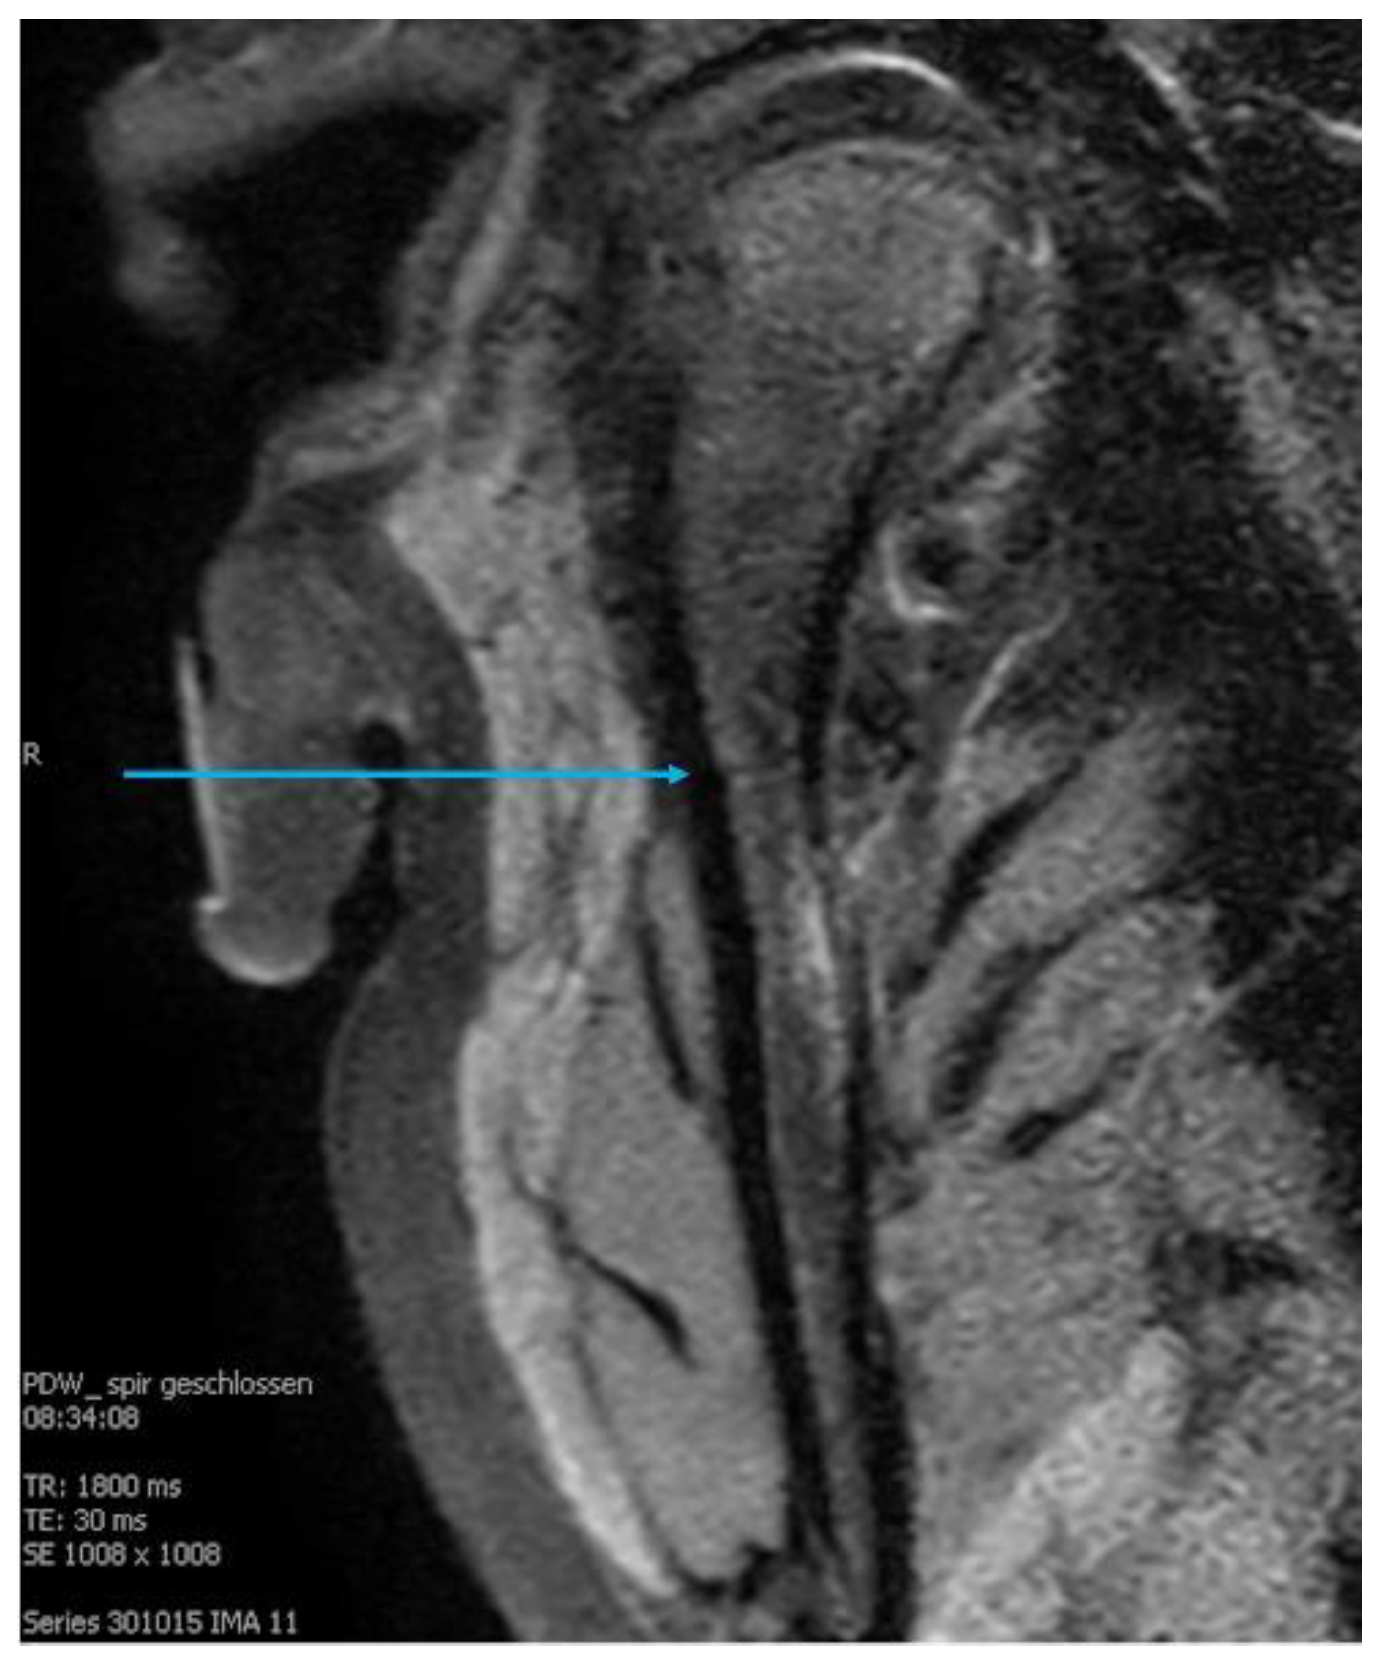

3.3. Radiological Findings